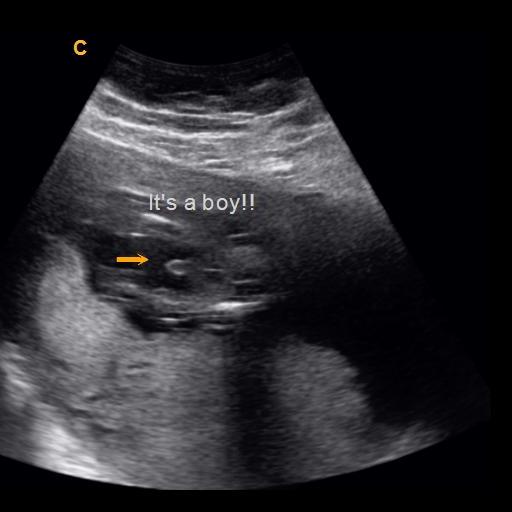

what does a boy look like on ultrasound

A 20 Week Male Gender Guess | Ultrasound Unwrapped

Gender Ultrasound..boy? {picture} | BabyCenter